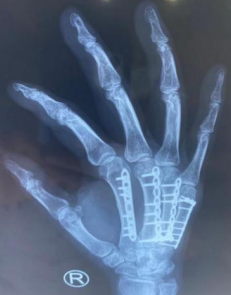

术中

最终,患者选择了钢板内固定的手术方式。完善各项术前准备工作,熊医师手术团队为患者进行了右2-5掌骨骨折切开复位内固定术,术中手法复位骨折断端,观察对位良好,使用钢板内固定,手术顺利。术后,医护团队在护理上指导患者注意患肢休息,加强功能锻炼,局部热敷促进血液循环,同时饮食清淡,多喝牛奶和吃新鲜水果,促进钙质的吸收,患者恢复良好。